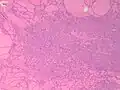

Fine-needle aspiration for cytology is generally not indicated in an autonomously functioning thyroid nodule, as the risk of malignancy is low, and it is generally difficult to distinguishing between a benign lesion and a malignant lesion in such specimens.[8] If thyroidectomy is performed, histopathology can corroborate the diagnosis. Toxic multinodular goiter more or less corresponds to diffuse or multinodular hyperplasia of the thyroid (Grave's disease also shows hyperplasia, but typically more prominent thickening of follicular linings):

Diffuse thyroid hyperplasia typically shows variably sized follicles

Thyroid hyperplasia with a hyperplastic nodule. It characteristically has no capsule (distinguishing it from thyroid adenoma or carcinoma).

The follicular linings may be thickened, with papillary projections (but lack nuclear features of papillary thyroid carcinoma)

The epithelium may also be flattened by enlarged follicles.

It can show hypercellular or microfollicular areas. There is no surrounding capsule (in contrast, a thyroid follicular adenoma or carcinoma is generally encapsulated).

As shown in these microfollicles, it can have mildly enlarged nuclei with mildly clumped chromatin, and clear cytoplasms, but cellular characteristics of papillary thyroid carcinoma are absent.

Thyroid hyperplasia with a Sanderson polster, which is a group of small follicles that protrude into the lumen of a larger follicle. It should not be confused for papillary projections.

Various forms of degeneration are typically seen, with various forms pictured.